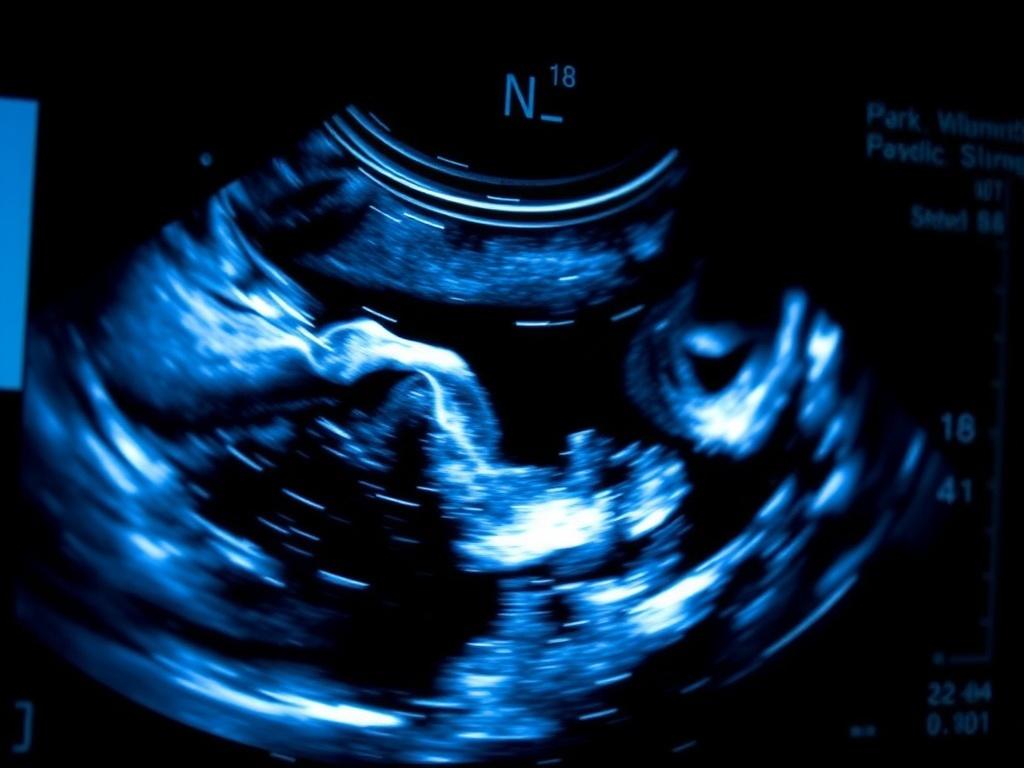

L’échographie pratiquée au tout début de la grossesse joue un rôle central : donner une date fiable et vérifier que l’embryon se développe comme attendu. Cet examen, souvent chargé d’émotion pour les parents, mêle technique et interprétation clinique. Il permet d’établir l’âge gestationnel, d’identifier la présence d’activité cardiaque et d’orienter la prise en charge ultérieure.

Le geste échographique suit des étapes classiques : localiser le sac gestationnel dans la cavité utérine, documenter la présence ou l’absence de vésicule vitelline, rechercher le pôle embryonnaire, puis mesurer le crown‑rump length (CRL) et détecter l’activité cardiaque. Une coupe sagittale du fœtus, avec alignement tête‑corps, est la référence pour la mesure du CRL.

Le CRL, distance entre le sommet de la tête et la partie la plus basse du tronc, reste la référence pour estimer l’âge gestationnel au premier trimestre. Sa précision est remarquable pendant les premières semaines, avec une marge d’erreur qui augmente ensuite.

En pratique, une mesure fiable du CRL permet souvent de dater la grossesse à quelques jours près, bien plus précisément que le calcul sur la date des dernières règles. Pour la cohérence des dossiers, il est important d’indiquer la méthode de mesure et l’appareil utilisé.

La détection d’un rythme cardiaque embryonnaire est le facteur le plus rassurant. Quand le scan montre un embryon avec activité cardiaque conforme à l’âge présumé, le pronostic immédiat est bon pour la poursuite de la grossesse. La datation précise sert ensuite de référence pour les examens du second trimestre et pour la prévision de la date d’accouchement.

Un souvenir marquant : lors d’un examen transvaginal, la découverte d’un rythme cardiaque très précoce a transformé une salle d’attente silencieuse en sourires et larmes de soulagement. Ce petit détail visuel, que la technologie rend accessible, a une portée humaine considérable.